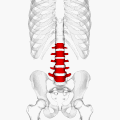

![]() Положение поясничных позвонков человека (отмечены красным). Пять позвонков обозначаются (сверху вниз) L1, L2, L3, L4 и L5. | |

Поясни́чные позвонки́ (лат. vertebrae lumbales) — пять нижних позвонков у человека с 20-го по 24-й, считая сверху. Поясничный отдел позвоночника соединяется ниже с крестцом (нижний поясничный позвонок L5 соединяется с верхним крестцовым позвонком S1), выше — с грудным отделом позвоночника (L1 соединяется с нижним грудным позвонком Th12).